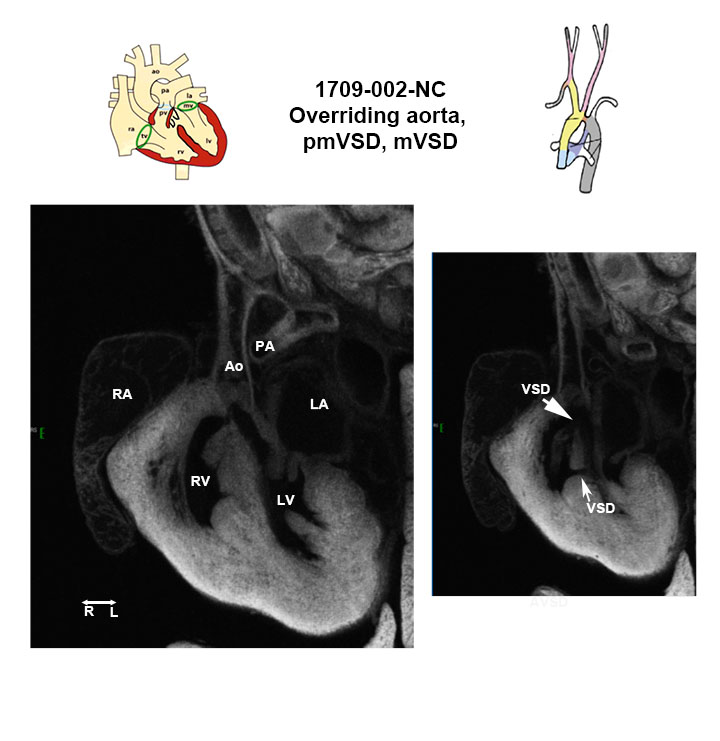

Caption EFIC Summary

Copyright This image is from the Laboratory of Dr. Cecilia Lo, a member of the Cardiovascular Development Consortium (CvDC), Bench to Bassinet (B2B) program of the National Heart Lung and Blood Institute (NHLBI), and is displayed with the permission of the authors. J:175213

b2b1709Clo Mutant line 1709; Bench to Bassinet Program (B2B/CVDC), mutation 1709 Cecilia Lo

b2b1709Clo/b2b1709Clo C57BL/6J-b2b1709Clo